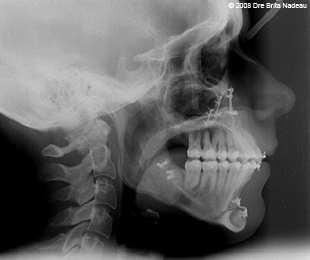

- 15 MARS 2008 - Ma chirurgie (2 jours avant ma première chirurgie)